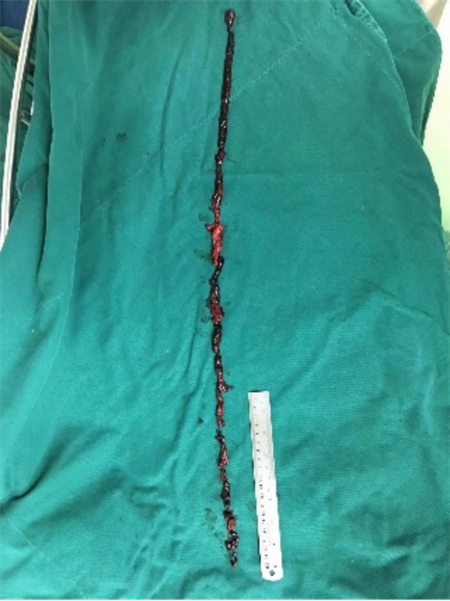

入院后,经过血管外科医师详细检查,诊断患者为左下肢动脉栓塞,其原因是因为房颤没有正规治疗,心脏里面形成血栓,血栓脱落掉到了下肢,造成了下肢动脉栓塞。如果不及时处理,可能导致下肢缺血加重,甚至出现肢体坏死乃至需要截肢。在完善了术前准备后,肝胆外科血管组医生连夜对患者实施了左下肢动脉切开取栓,术后效果立竿见影,患者下肢的疼痛消失,感觉逐渐得到恢复,住院几天后患者便高高兴兴地回家了。

CTA见左下肢动脉栓塞